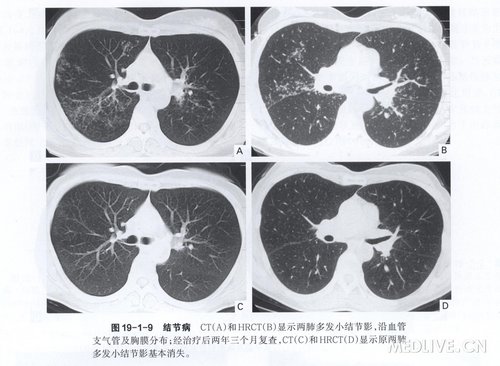

2.CT表现双侧肺门淋巴结对称性肿大为最典型的CT表现(图19-1-3)。另外,病变早期,非特异性间质性肺泡炎在CT上表现为斑片状阴影或毛 玻璃样改变,肺实质可见云雾状的轻度密度增高影(图19-1-4),其内的血管和支气管隐约可见;病变进一 步发展所形成的非干酪性肉芽肿,在CT上表现为沿血管和支气管走行分布的粟粒状结节影(图19-1-5),直径多为1—5 mm,边缘光滑;非干酪性肉芽肿也可位于肺外围、小叶间隔或斜裂附近的胸膜下,表现为血管、支气管串珠状增粗及小叶间隔串珠状增厚(图19 -1-6)。因此,在HRCT上,结节病的肺内粟粒样结节影沿淋巴道分布,即沿支气管血管束、 小叶中心、小叶间隔及胸膜面分布。粟粒样结节影的分布通常呈两侧对称性,但也可呈以单侧分布为主(图19 -1-7)。结节病肺内也可见小结节影(图19 -1-8),部分可发生融合形成较大结节影。当云雾状斑片影和结节影同时出现时,常提示活动性肺泡炎向肉芽肿过渡。病变晚期,间质纤维化形成,CT 表现为小叶结构扭曲、肺门及斜裂移位、牵张性支气管扩张移位及网状致密影等。CT还有助于追踪观察,以判断疗效(图19 -1-9)。